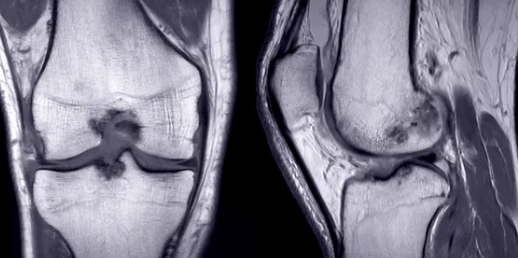

3. 무릎 관절삼출 진단 방법

✅ 병원에서 진행하는 주요 진단 검사

검사 방법 설명

| X-ray 검사 | 무릎 관절의 골절, 뼈의 이상 여부 확인 |

| MRI 검사 | 연골 손상, 인대 파열, 관절 내 염증 확인 |

| 초음파 검사 | 무릎 내부의 염증 및 관절액 증가 여부 평가 |

| 혈액 검사 | 류마티스 관절염, 통풍 등의 염증 수치 확인 |

| 관절액 검사 (관절천자) | 주사기로 관절액을 채취하여 감염 여부, 염증 원인 분석 |

📌 TIP:

- 무릎 관절염과 연골 손상 여부를 구별하기 위해 MRI 검사가 효과적입니다.

- 류마티스 관절염이나 감염성 관절염이 의심될 경우, 혈액 검사 및 관절액 검사가 필수적입니다.